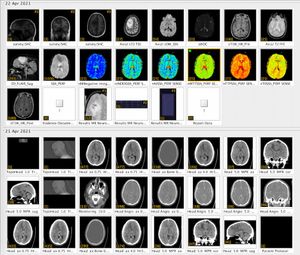

Obtained my full scan data - Tuesday 25th May

I received an automated email saying this could take up to 28 days, but 2 days later I had an email from a member of the team saying that my scans were scheduled for the overnight upload and I'd receive the link the following day. Upon receiving the link they sent me a one time password (OTP) via my mobile number that allowed me to login. The web performance of the system was shocking. Took around 20 seconds to load on a 50 Mbit connection and a modern browser! Thank you JavaScript...

Once I clicked on the download button I realised this wasn't just a set of high resolution images, as it was a zip file for 1.3 GB of data! Intriguing! It took me a number of attempts to actually download the data, and I had close friends try too. Their server connection was slow and unreliable, and it also doesn't seem to support HTTP range requests, so it wasn't possible to resume a download after already managing to grab 880 MB of it! Best thing to do I found was to wait until later in the evening. I managed to get a download speed of around 2.7 MB per second, so it only took around 15 minutes in the end.

The reason the zip file is so huge is because it is sent in a standardized format for use in specialist tools that can interpret the data. Here's me thinking it would be just a few images... nope! It's literally all the images from all scans completed so far! Hence the box on the form stating which scans you require.

I believe there are around 4,000-5,000 images in total from 1 CT and 1 MRI scan! Thankfully there are tools that you can use to view these images. And not just view them, they allow you to navigate through all the scans. Each image is essentially a "slice" of the brain. The tools allow you to move through all 3 axis in near real time, with each of the corresponding panels changing depending on the input from the others.

In the above image you can see my MRI scan. It's essentially an orthogonal view of my head, with each of the panels represents a different axis:

- Left panel: Top of my head (Axial view)

- Top right: Front to back of my head (Coronal view)

- Bottom left: Side of my head (Sagittal view)

The solid blue line you see in the views is the current plane I have selected to see. As you move this plane, all three images change accordingly. Notice how the blue line on the axial view (left panel) matches that of the coronal view (top right) in terms of position. The resulting image in the sagittal view (bottom left) is the image that corresponds with this selection I have made.

It's so incredibly clever and absolutely fascinating (to me at least)! I spent the best part of 2-3 hours looking at my own brain scans. I wish I knew what it all meant, but I plan on quizzing the experts when I get the chance. I'd like to write a blog post all about it in the future. So, watch this space!

For those interested in doing the same the tools I used are:

Horos takes it a step further, as it allows you to view your scan in 3D, and even export an animation to show all your friends at the next soirΓ©e you attend! So yes, if you ever fancy looking at your own insides in detail, remember you can request your CT and MRI scan data!